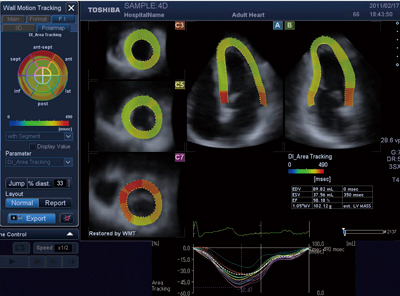

3d Wall Motion Tracking技術の特長と最新動向 東芝メディカルシステムズ株式会社 Innavi Suite

Artida の最新壁運動解析技術 東芝メディカルシステムズ株式会社 Innavi Suite